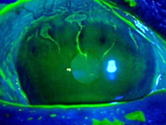

抗がん剤(S-1)を3ヶ月使用中でした。左は初診時の角膜です。

上方に角膜の障害があります。 右は抗がん剤を中止して2週間後です。

傷が浅く小さくなっています。 2ヶ月して正常な状態になりました。